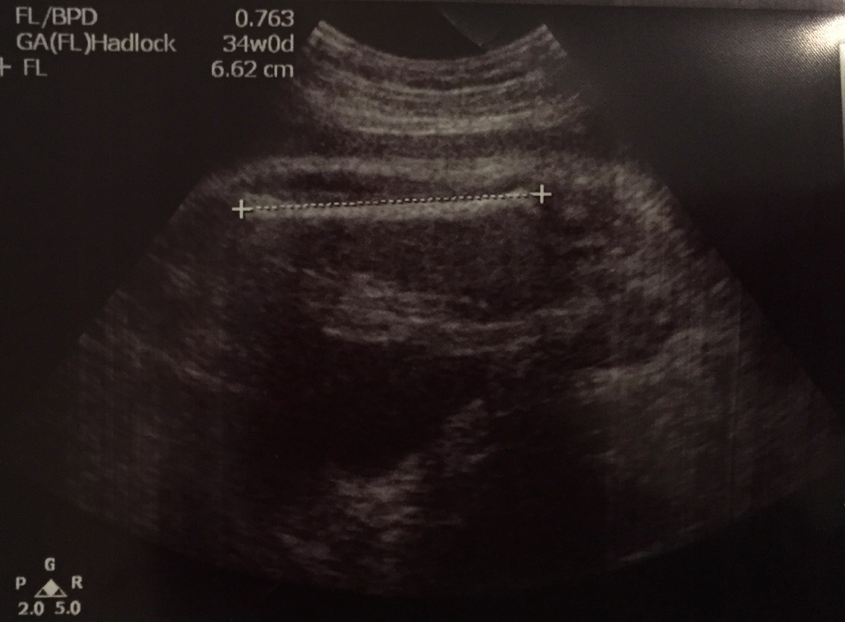

繼續長腿嘅6.62cm﹗

plot落graph就更加一目了然了~各方面都穩步成長中﹗繼續係莫名奇妙嘅長腿囉~:p用今日嘅parameters嚟計,現時呢一刻嘅估計體重係2.7kg﹗75-90 percentile之間~如果按呢個趨勢生長,足月的話肯定超過7磅啦~講起呢樣,原來之前同奶奶傾開先知道佢好擔心BB長得唔大,佢成日都覺得我個肚唔係好大個,所以之前我都show過growth chart嗰啲俾佢睇希望佢放心,但結果令佢放心嘅居然唔係呢啲客觀數據而係我個「裸肚」,睇過我哋啲maternity photo佢就好安樂啦(請參閱:14-3-2015:懷孕扎記34w0d.maternity photography@SENS Studio之成品篇),原來個肚都幾大~:p